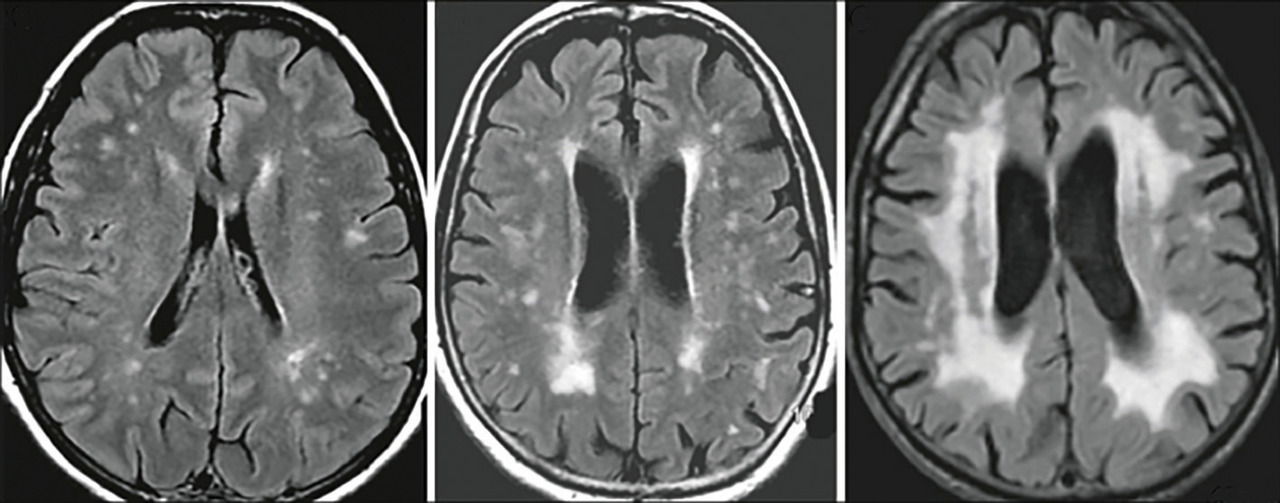

En dehors de cette situation, des ischémies sous- corticales répétées sont parfois à l’origine d’une leucoaraiose périventriculaire (fig. 4) qui n’est pas spécifique mais qui témoigne de l’étendue des lésions ischémiques. Certains tableaux de dépression de la personne âgée avec des facteurs de risque cardiovasculaire, marqués par une apathie et des troubles cognitifs, s’associent à une leucoaraiose diffuse (on parle de dépression vasculaire).

– l’IRM peut montrer une atrophie diffuse ou de l’hippocampe (fig. 5) et/ou des lésions de leucoaraiose ;